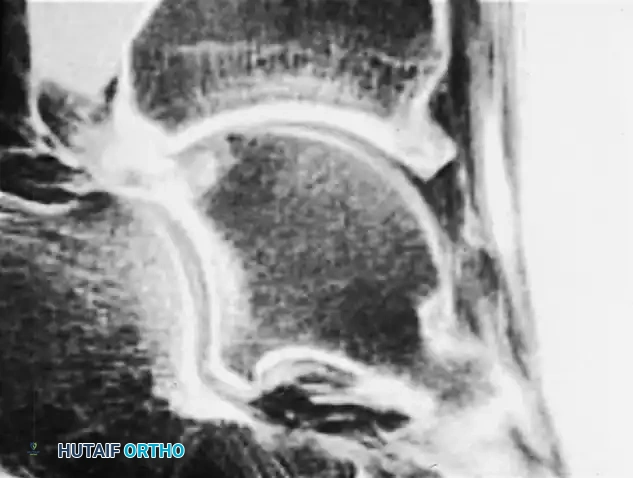

Standard weight-bearing radiographs (anteroposterior, lateral, and mortise views) are mandatory. The lateral view is particularly diagnostic for anterior impingement, revealing a loss of the normal rounded contour of the anterior distal tibia, replaced by a sharp ridge or a distinct anteriorly projecting bony spur. Corresponding dorsal talar spurs may also be visible.

Advanced imaging, such as MRI or CT arthrography, is highly valuable for identifying radiographically occult soft tissue impingement. CT arthrography provides excellent visualization of nodular formations in the lateral groove (often resembling discoid meniscal lesions) and abundant fibrous reactions. Furthermore, MRI can identify "tram track" lesions—parallel linear chondral defects on the talar dome caused by the abrasive action of tibial osteophytes—which aid in pinpointing the exact location of the impingement.